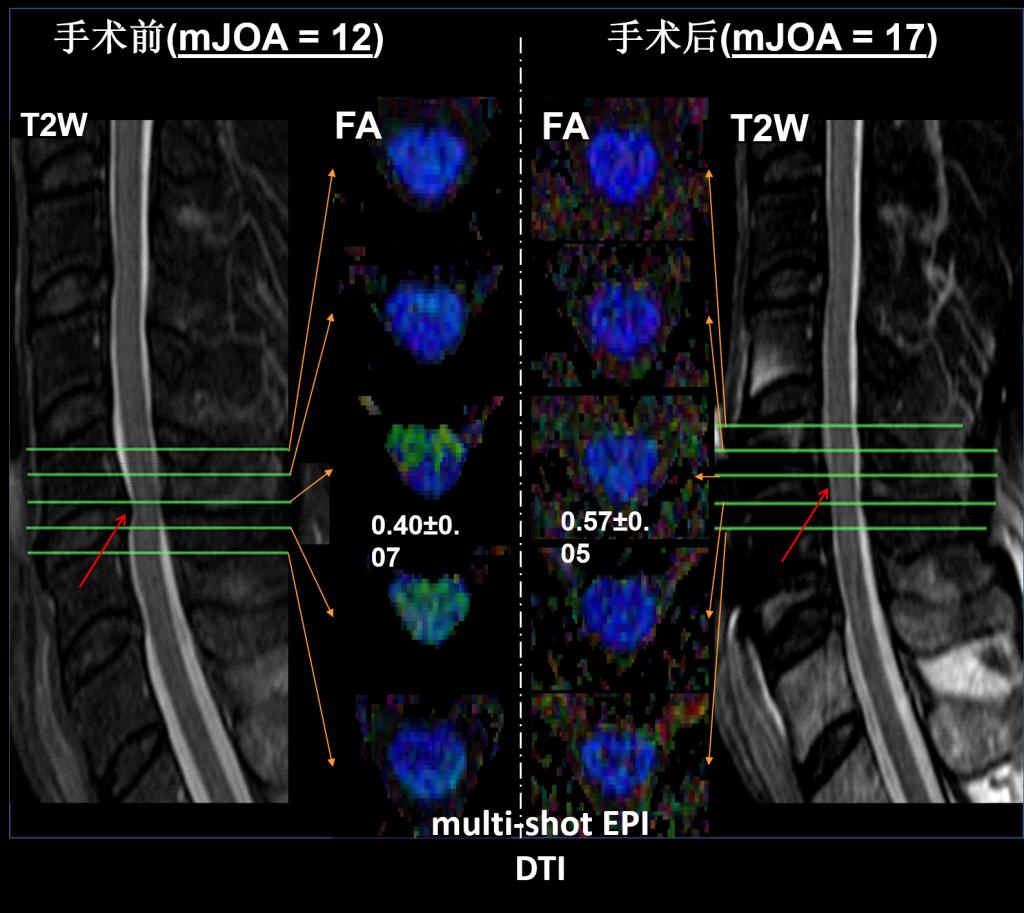

影像中心自成立以来,承担了科技部、国家自然科学基金委、卫生部、北京市科委等近百项国家和省部级项目,收到各种研究经费支持达5000万余元,已发表论文600余篇,发明专利60余项,国际专利10余项,培养学生130余人,获得各种奖励30余项。影像中心已成为全球重要的医学影像尤其是磁共振技术研发中心,开发出大视野高分辨血管壁多对比度成像、三维心肌定量成像、定量血流成像、定量生理成像、无变形高分辨率弥散成像等诸多原创技术,同时这些技术被广泛地应用在多项大规模临床人群队列研究当中形成了针对心脑血管、神经变性性疾病等原创性影像学解决方案。